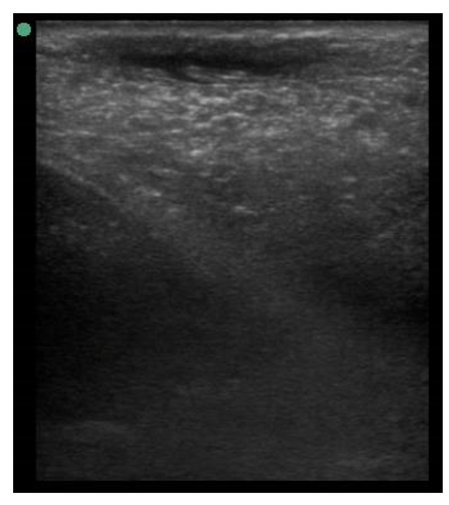

The image processing was undertaken using ImageJ software [28] as used by Abràmoff et al. [29]. The scales between pixels and millimetres were calculated based on the number of pixels, the scanning depth (mm), and the transducer width (mm) (Figure 4). This method relies on the ability of the operator to interpret and identify lines on the images. To standardize the assessment compartment depth, drawing templates were created for each time point as used by Molenaar et al. [30] and included four representative images from four different yearling ewes with and without the lines drawn for each compartment (Appendix A). The total depth of mammary gland conservative (MTc) was the smallest likely demarcation (abdominal wall) of the mammary gland (Figure 5a), and total depth of the mammary gland generous (MTg) was the largest likely demarcation of the mammary gland visible on the image [30] (Figure 5a). The MTc, MTg, fat pad (FP), parenchyma (PAR), and gland cistern (GC) depths were estimated at the deepest point for each sub-compartment, excluding the skin layers, using the straight tracer (Figure 5a) and were expressed in millimetres.

Figure 5.

(a) Demonstration of delimitations of the mammary total depth conservative (MTc) and generous (MTg), mammary gland cistern (GC), parenchyma (PAR) and the fat pad (FP) and (b) Demonstration of randomly positioning of regions of interest (1, 2, 3) in the parenchyma.

Drawing template of mammary ultrasound images in early lactation (29 days of lactation; L29) in four different yearling ewes.